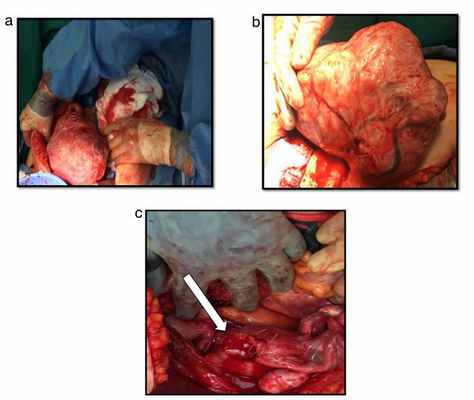

В данном случае рассмотрим конкретный пример полностью вывернутой шейки матки из-за выпавшей огромной лейомиомы шейки матки, имитирующей хроническую послеродовую инверсию матки у женщин в перименопаузе.

52-летняя женщина в перименопаузе поступила в нашу клинику с изъязвленным, некротическим, инфицированным и опухшей выпавштим образованием, происходящим из влагалища.

Беременности – 4, родов – 3, аборт – 1.

Из анамнеза: диагностирована миома матки 5 см в диаметре 2 года назад. Было предложено оперативное лечение, от которого она отказалась.

За 6 месяцев до описанный событий отметила появление образования из влагалища. За медицинской помощью так же не обращалась. На настоящий момент обратилась в больницу в связи с появлением изъязвлений на образовании, некупируемого болевого синдрома. Пациентке была выполненена гистерэктомия вагинальным доступом. Окончательный диагноз был поставлен уже интраоперационно.

а) некротизированный миоматозный узел

б) вывернутая шейка матки

а) матка

б) область наружного зева шейки матки

в) перевернутая шейка матки

г) лейомиома

а) нормальный миометрий и полость матки

б) перевернутая шейка матки

в) миома шейки матки